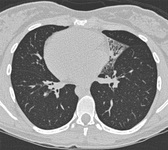

Bronquiectasia

Sinais do anel de sinete em uma mulher de 20 anos de idade com bronquiectasia

De Pamela J. McShane, MD; uso autorizado